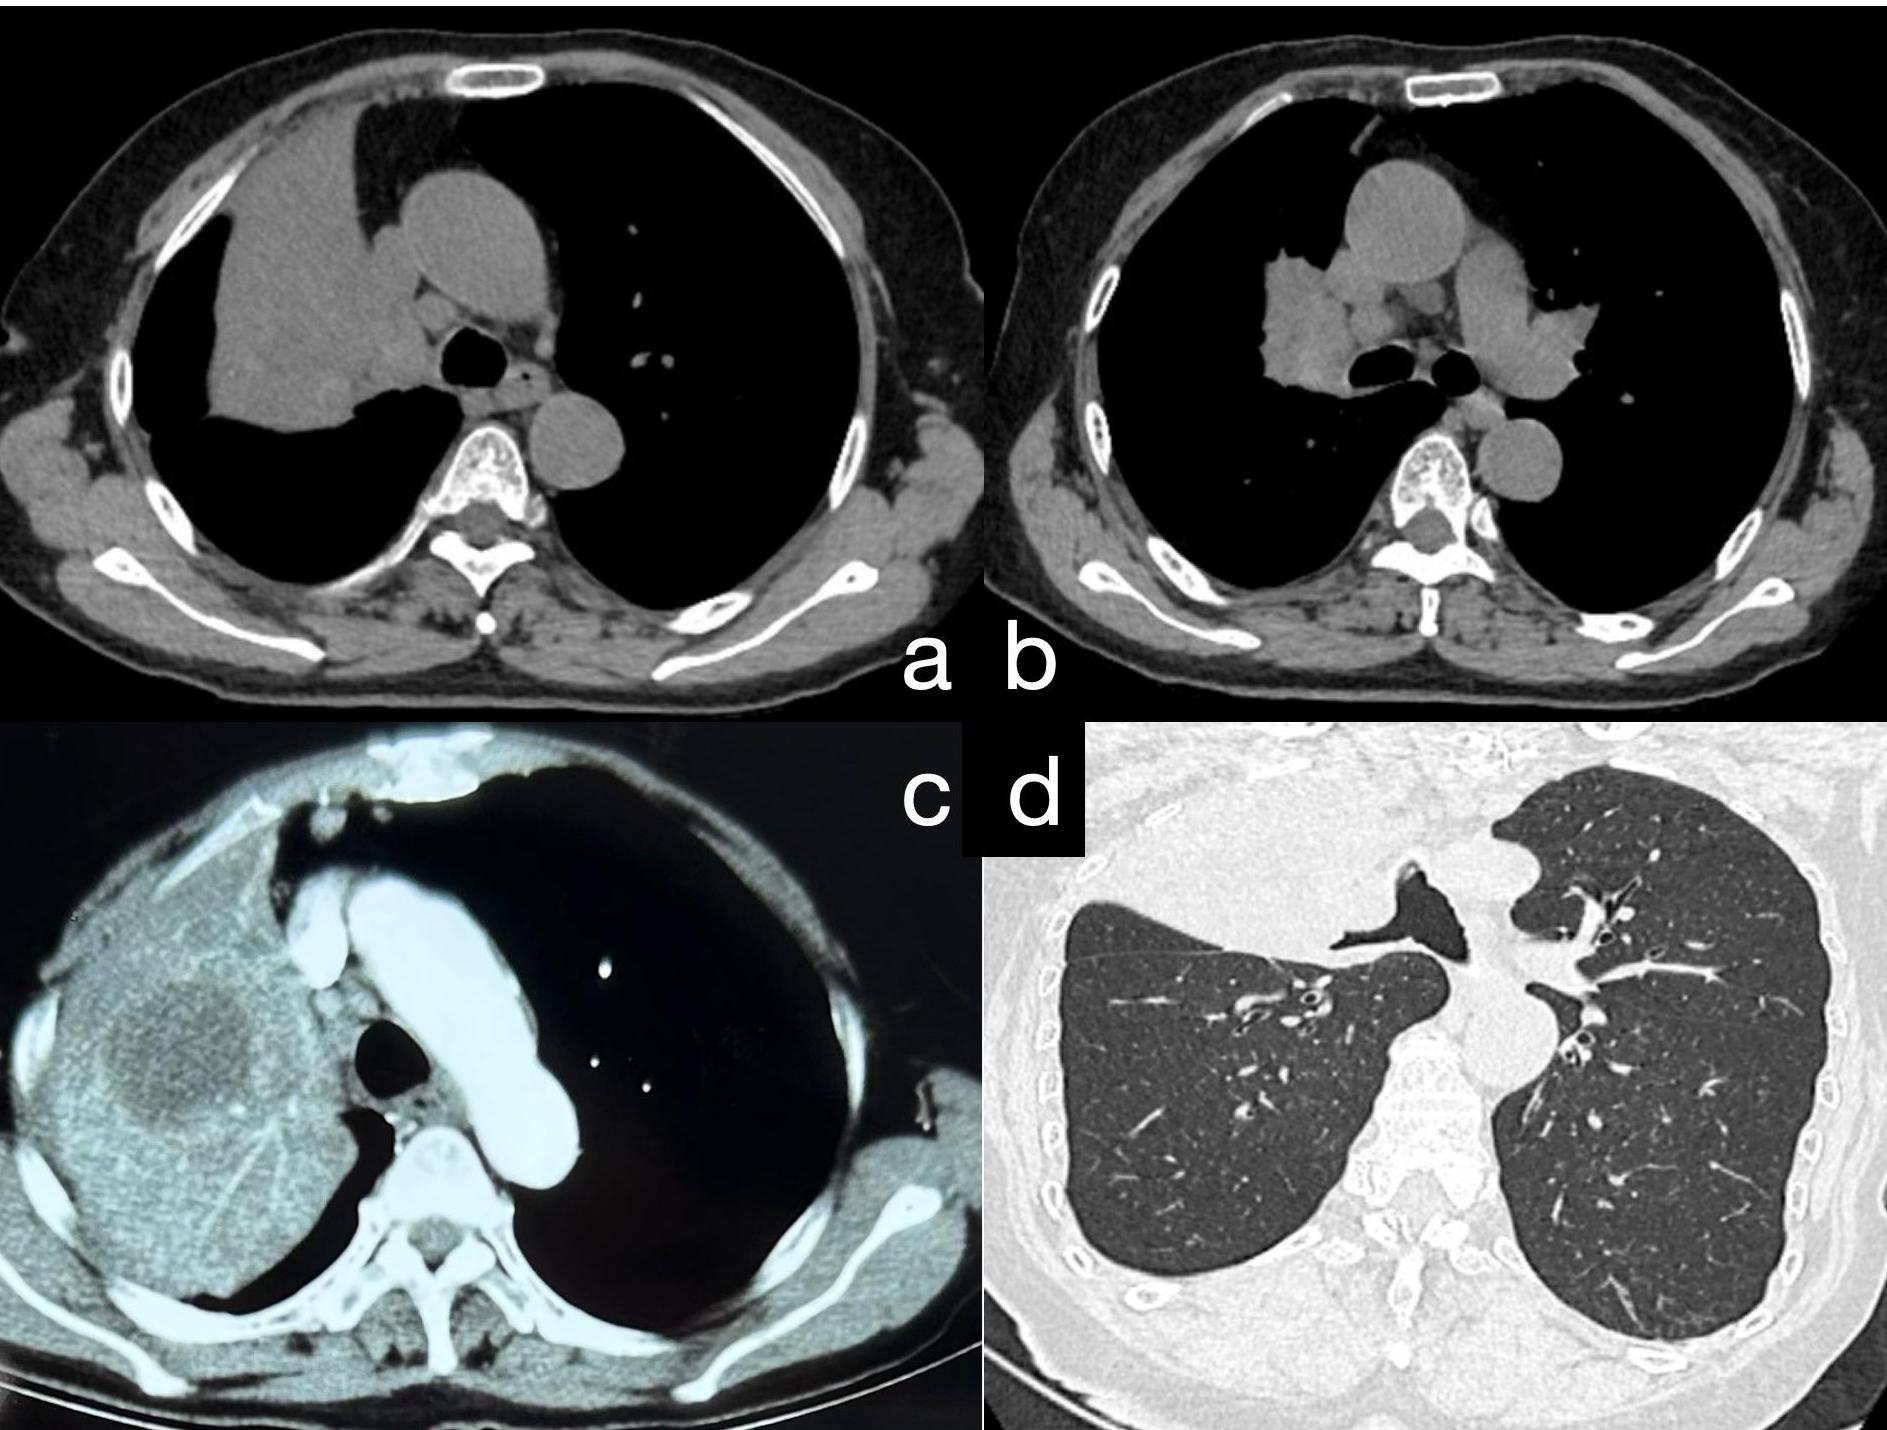

A 75-year-old female patient was admitted to our hospital with recurrent fever, cough, and sputum production for over 8 months. The patient had a 30-pack-year smoking history and had quit smoking 6 months prior. She denied a history of hypertension, coronary artery disease, diabetes, or other chronic illnesses, as well as any abnormal personal, familial, or other psychosocial medical history. She underwent a CT-guided percutaneous lung biopsy at another hospital 1 month ago, with pathology suggesting inflammation (Supplementary Material S1). She underwent 1 week of anti-inflammatory treatment, but the effects were not significant; her symptoms of cough, expectoration, and fever persisted. When we admitted her, a physical examination revealed no signs of jaundice, bleeding, or rash on either the skin or mucous membranes. The superficial lymph nodes were not palpable or enlarged. Chest wall symmetry was maintained, with normal respiratory excursions and rhythmic breathing patterns. Auscultation revealed moist rales in the right upper lung field and slightly coarse breath sounds in the right lower and left lung fields, with no pleural friction rubs detected. No evidence of digital clubbing was found, and no peripheral edema was observed. An enhanced chest CT scan showed a large consolidation shadow in the right upper lobe, with a central ring of low density (Figure 1). Subsequently, the patient’s sputum was subjected to microbiological culture, which yielded negative results.

Figure 1

(A) Chest CT reveals a large area of consolidation in the upper lobe of the right lung. (B) Consolidation in the upper lobe of the right lung accompanied by multiple enlarged mediastinal lymph nodes. (C) Postcontrast chest CT demonstrates moderate enhancement in the consolidated area of the upper lobe of the right lung, with quasi-round, slightly hypodense lesions within the focus; the boundaries are still clear. (D) Following 3D reconstruction of the chest CT, bronchial narrowing and obstruction in the upper lobe of the right lung are evident.

The imaging features of HAL are nonspecific and lack typical characteristics. Most lesions are large (3.5–11 cm) and present primarily in the upper lobes, near the pleura or mediastinal pleura, often adjacent to the chest wall or major blood vessels (10). Enhanced CT typically shows necrotic changes (11), which is easily confused with pulmonary tuberculosis (12). Our patient underwent a CT-guided percutaneous lung biopsy at another hospital, which was suggestive of inflammation, although subsequent special stains for inflammation were negative. We noted a low-density area within the lesion center, possibly indicative of necrosis, which could lead to noninfective inflammation consistent with the characteristics of HAL. We speculate that the tissue obtained during her first biopsy might have originated from this necrotic zone, resulting in a false-negative outcome. However, serum marker testing or immunohistochemistry of lesion tissue can aid differentiation. Our patient’s CT showed a large lesion (10.7 cm) in the right upper lobe with central necrosis, typical of HAL. In the initial biopsy, necrotic tissue was likely obtained, causing a misdiagnosis, while solid tumor tissue was successfully obtained in the second biopsy.